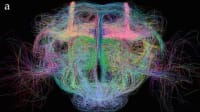

Search CHANNELS Aerospace Automotive Automated & Autonomous Vehicles Battery & Electrification Technology Defense Drone TV Electronics Manufacturing & Prototyping Materials Medical Motion Control RF & Microwave Technology Robotics & Automation Sensors & IoT Test & Measurement CHANNELS Aerospace Automotive Automated & Autonomous Vehicles Battery & Electrification Technology Defense Drone TV Electronics Manufacturing & Prototyping Materials Medical Motion Control RF & Microwave Technology Robotics & Automation Sensors & IoT Test & Measurement Aerospace & Defense Search Results Looking for Deep Brain Activation? Meet ImPULS Watch this video to learn more about an implantable piezoelectric ultrasound stimulator (ImPULS) that generates an ultrasonic focal pressure of 100 kPa to modulate the activity of neurons. Topics: Medical View the discussion thread. Transcript 00:00:06 [Music] [Music] a [Music] [Music] [Music]